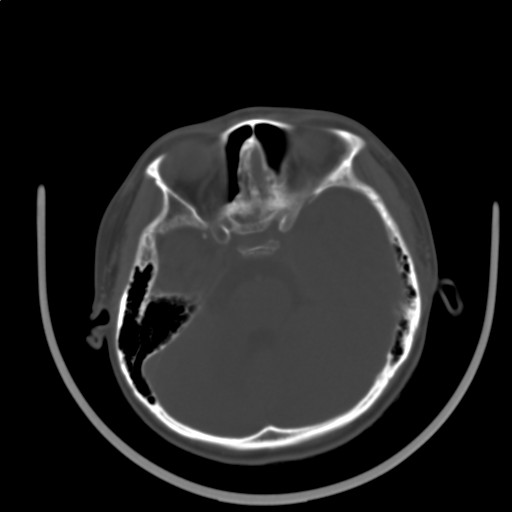

标题: PED3416:F,12Y,智力下降,学习成绩差,8个月时发过高烧。

右侧半球萎缩,软化,多量脑回样钙化,考虑颅面血管瘤病,建议dsa检查

右侧半球萎缩,软化,多量脑回样钙化,同侧颅盖板障增宽,考虑颅面血管瘤病,建议dsa检查与化脓性脑膜炎后遗改变鉴别。